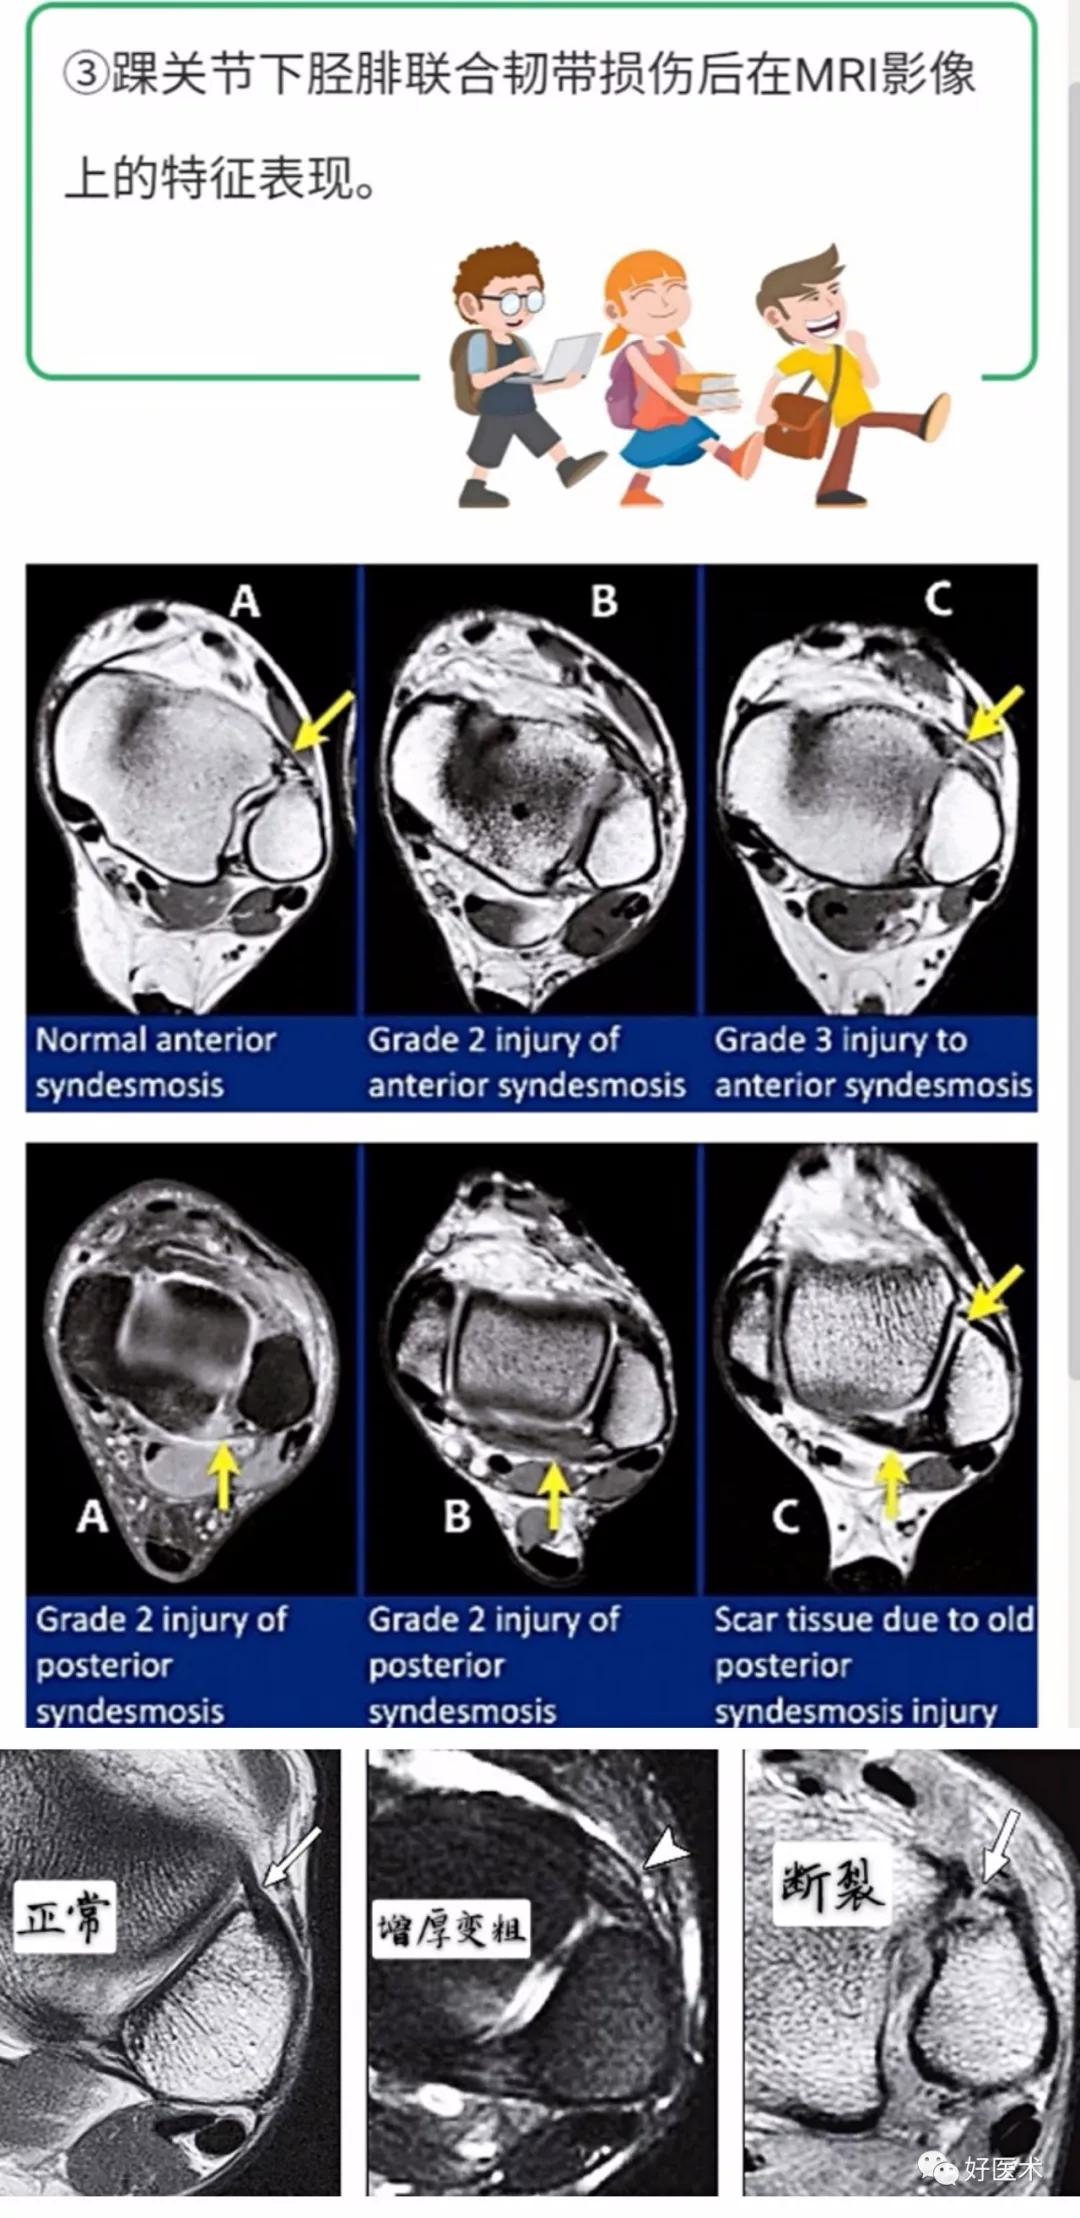

下胫腓韧带复合体

下胫腓韧带复合体包括下胫腓前韧带(AITFL)、下胫腓后韧带(PITFL)、骨间韧带(IOL)、下胫腓横韧带(TTL)以及骨间膜的远端部分。

下胫腓前韧带由胫骨下端的边缘向下外附着于外踝的前面及附近粗糙骨面上,主要限制腓骨外旋。

下胫腓后韧带则与下胫腓前韧带位置相当,纤维斜行,其下部纤维距胫骨下关节面尚有相当距离,因此使接受距骨的窝加深,恰好容纳距骨的后外侧部分,起到稳定距骨的作用,主要限制腓骨向后移动。

骨间韧带为短而坚实的纤维,实际上是骨间膜的向下延长部,纤维斜行,由内上方向外下方,起到加强胫腓骨的连结作用;

下胫腓横韧带横行于胫骨后面的下缘与外踝内侧面的三角间隙内,是加强的滑膜延长部,呈强韧索状,能防胫腓骨沿距骨上面向前脱位。

三、踝关节周围韧带异常的MRI特征